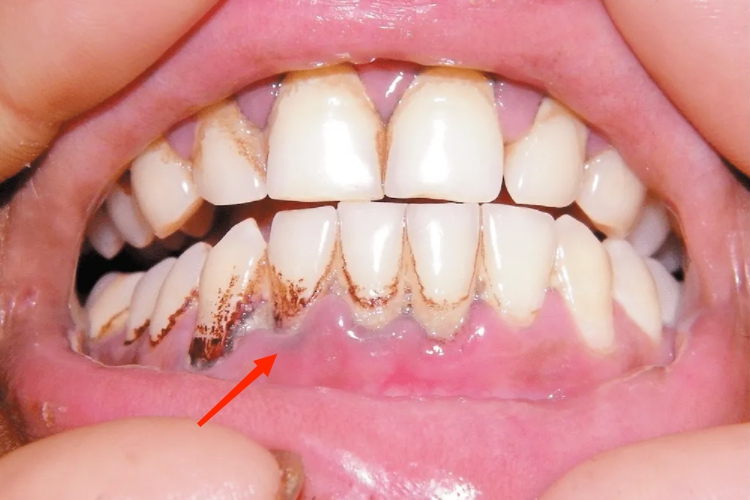

齿龈铅线是铅中毒的表现之一,在牙龈缘黏膜内可见硫化铅点状颗粒沉积形成的铅线,呈深灰色或蓝色的条带或不规则的斑块,多见于口腔卫生较差者。